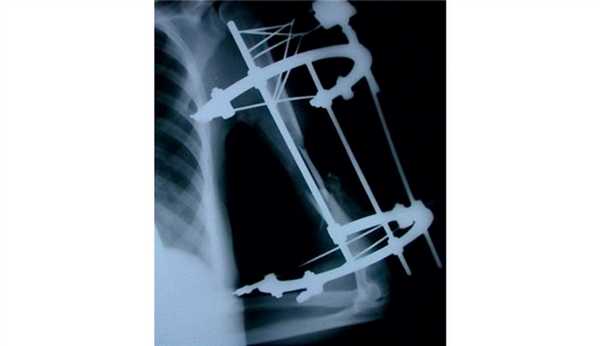

На рис. 3-9 Рис. 3. Пациентка И., 34 лет. Внешний вид до операции. Рис. 9. Внешний вид и функция через год после операции. представлены все этапы обследования и лечения пациентки И.

Рис. 5. Пациентка И. Этапное оперативное вмешательство. а — замещение дефекта плечевой кости цементным спейсером; б — транспозиция торакодорсального лоскута в область мягкотканного дефекта плеча; в — послеоперационная рентгенограмма.

Рис. 6. Рентгенограммы пациентки И. после удаления цементного спейсера.

Рис. 7. Оперативное лечение пациентки И.: пластика левой плечевой кости свободным кровоснабжаемым трансплантатом из малоберцовой кости.